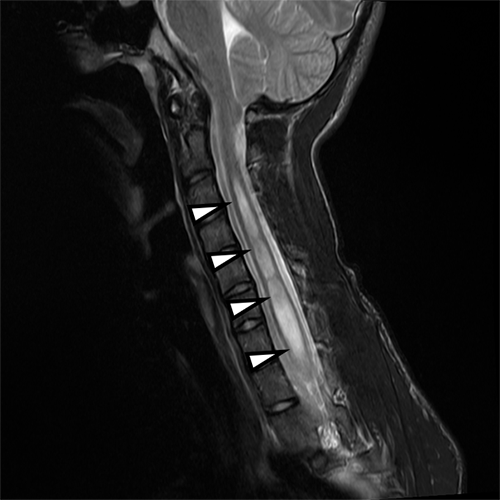

脊髄空洞症の単純MRI- 頚髄損傷

- 脊髄空洞症

脊髄・脊椎 (背骨の骨のこと) の疾患です。

脳から出ている神経の束が圧迫されたりすることで、手足のしびれ・麻痺などが起こることがあります。レントゲン・CT・MRIなどで検査し、どのように治療していくか検討していきます。整形外科でみていることも多い分野です。